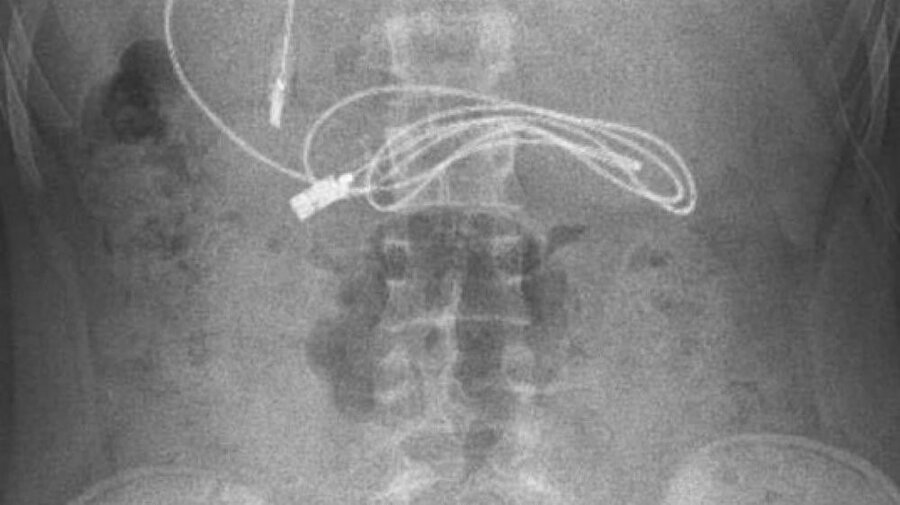

Diyarbakır'da kusma ve bulantı şikayetiyle hastaneye götürülen, çekilen röntgeninde 1 metrelik şarj kablosu ve toka yuttuğu tespit edilen 15 yaşındaki erkek çocuğu, Elazığ'da gerçekleştirilen operasyonla yuttuğu cisimlerden kurtuldu.

Diyarbakır'da kusma ve bulantı şikayetiyle ailesi tarafından hastaneye götürülen erkek çocuğunun çekilen röntgeninde, midesinde şarj kablosu ve toka olduğu tespit edildi.

Bunun üzerine çocuk, ambulans ile Fırat Üniversitesi Hastanesi'ne sevk edildi. Üniversitenin Çocuk Gastroenteroloji Hepatoloji ve Beslenme Bilim Dalı Başkanı Prof. Dr. Yaşar Doğan ve ekibi tarafından yapılan endoskopik işlemle çocuğun midesindeki kablo ve toka başarıyla çıkarıldı. Tedavisinin ardından sağlığına kavuşan çocuk taburcu edildi.

Ameliyatı gerçekleştiren Prof. Dr. Yaşar Doğan, kablonun bir ucunun ince bağırsağa geçmesi nedeniyle zorlandıklarını ifade ederek, “Hastanın kusma ve karın ağrısı şikayetleri olması üzerine sağlık kuruluşuna başvurulmuş. Orada yapılan incelemelerde hastanın midesinde kablo tespit edilmesi üzerine bize danışıldı.